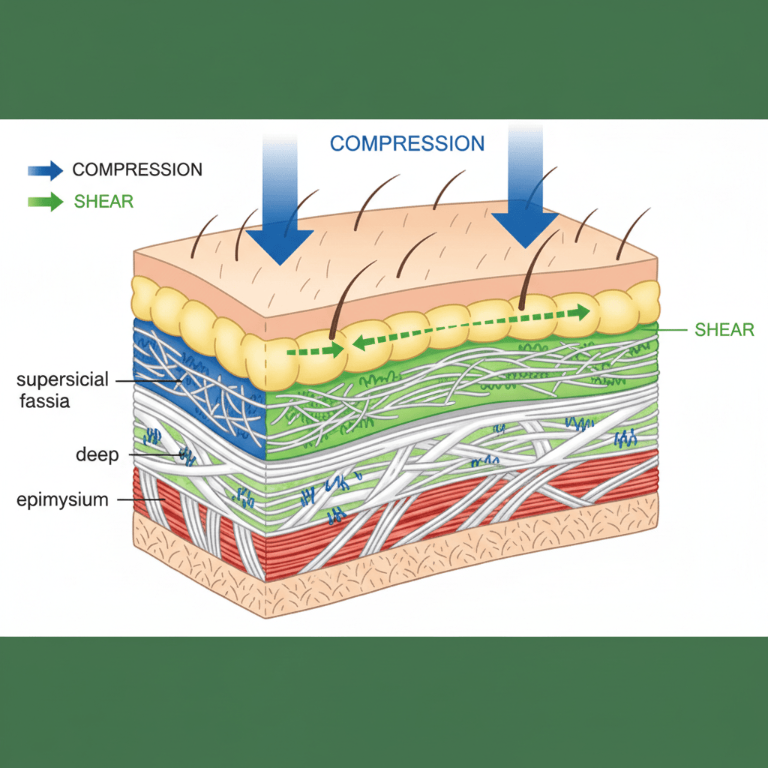

- Cross-fiber friction breaks collagen cross-links

- 3D vibration reaches deeper tissue layers (6-8mm penetration)

Mechanical Effects

- Rhythmic compression moves edema fluid

- 3D vibrations create microcurrents in tissue